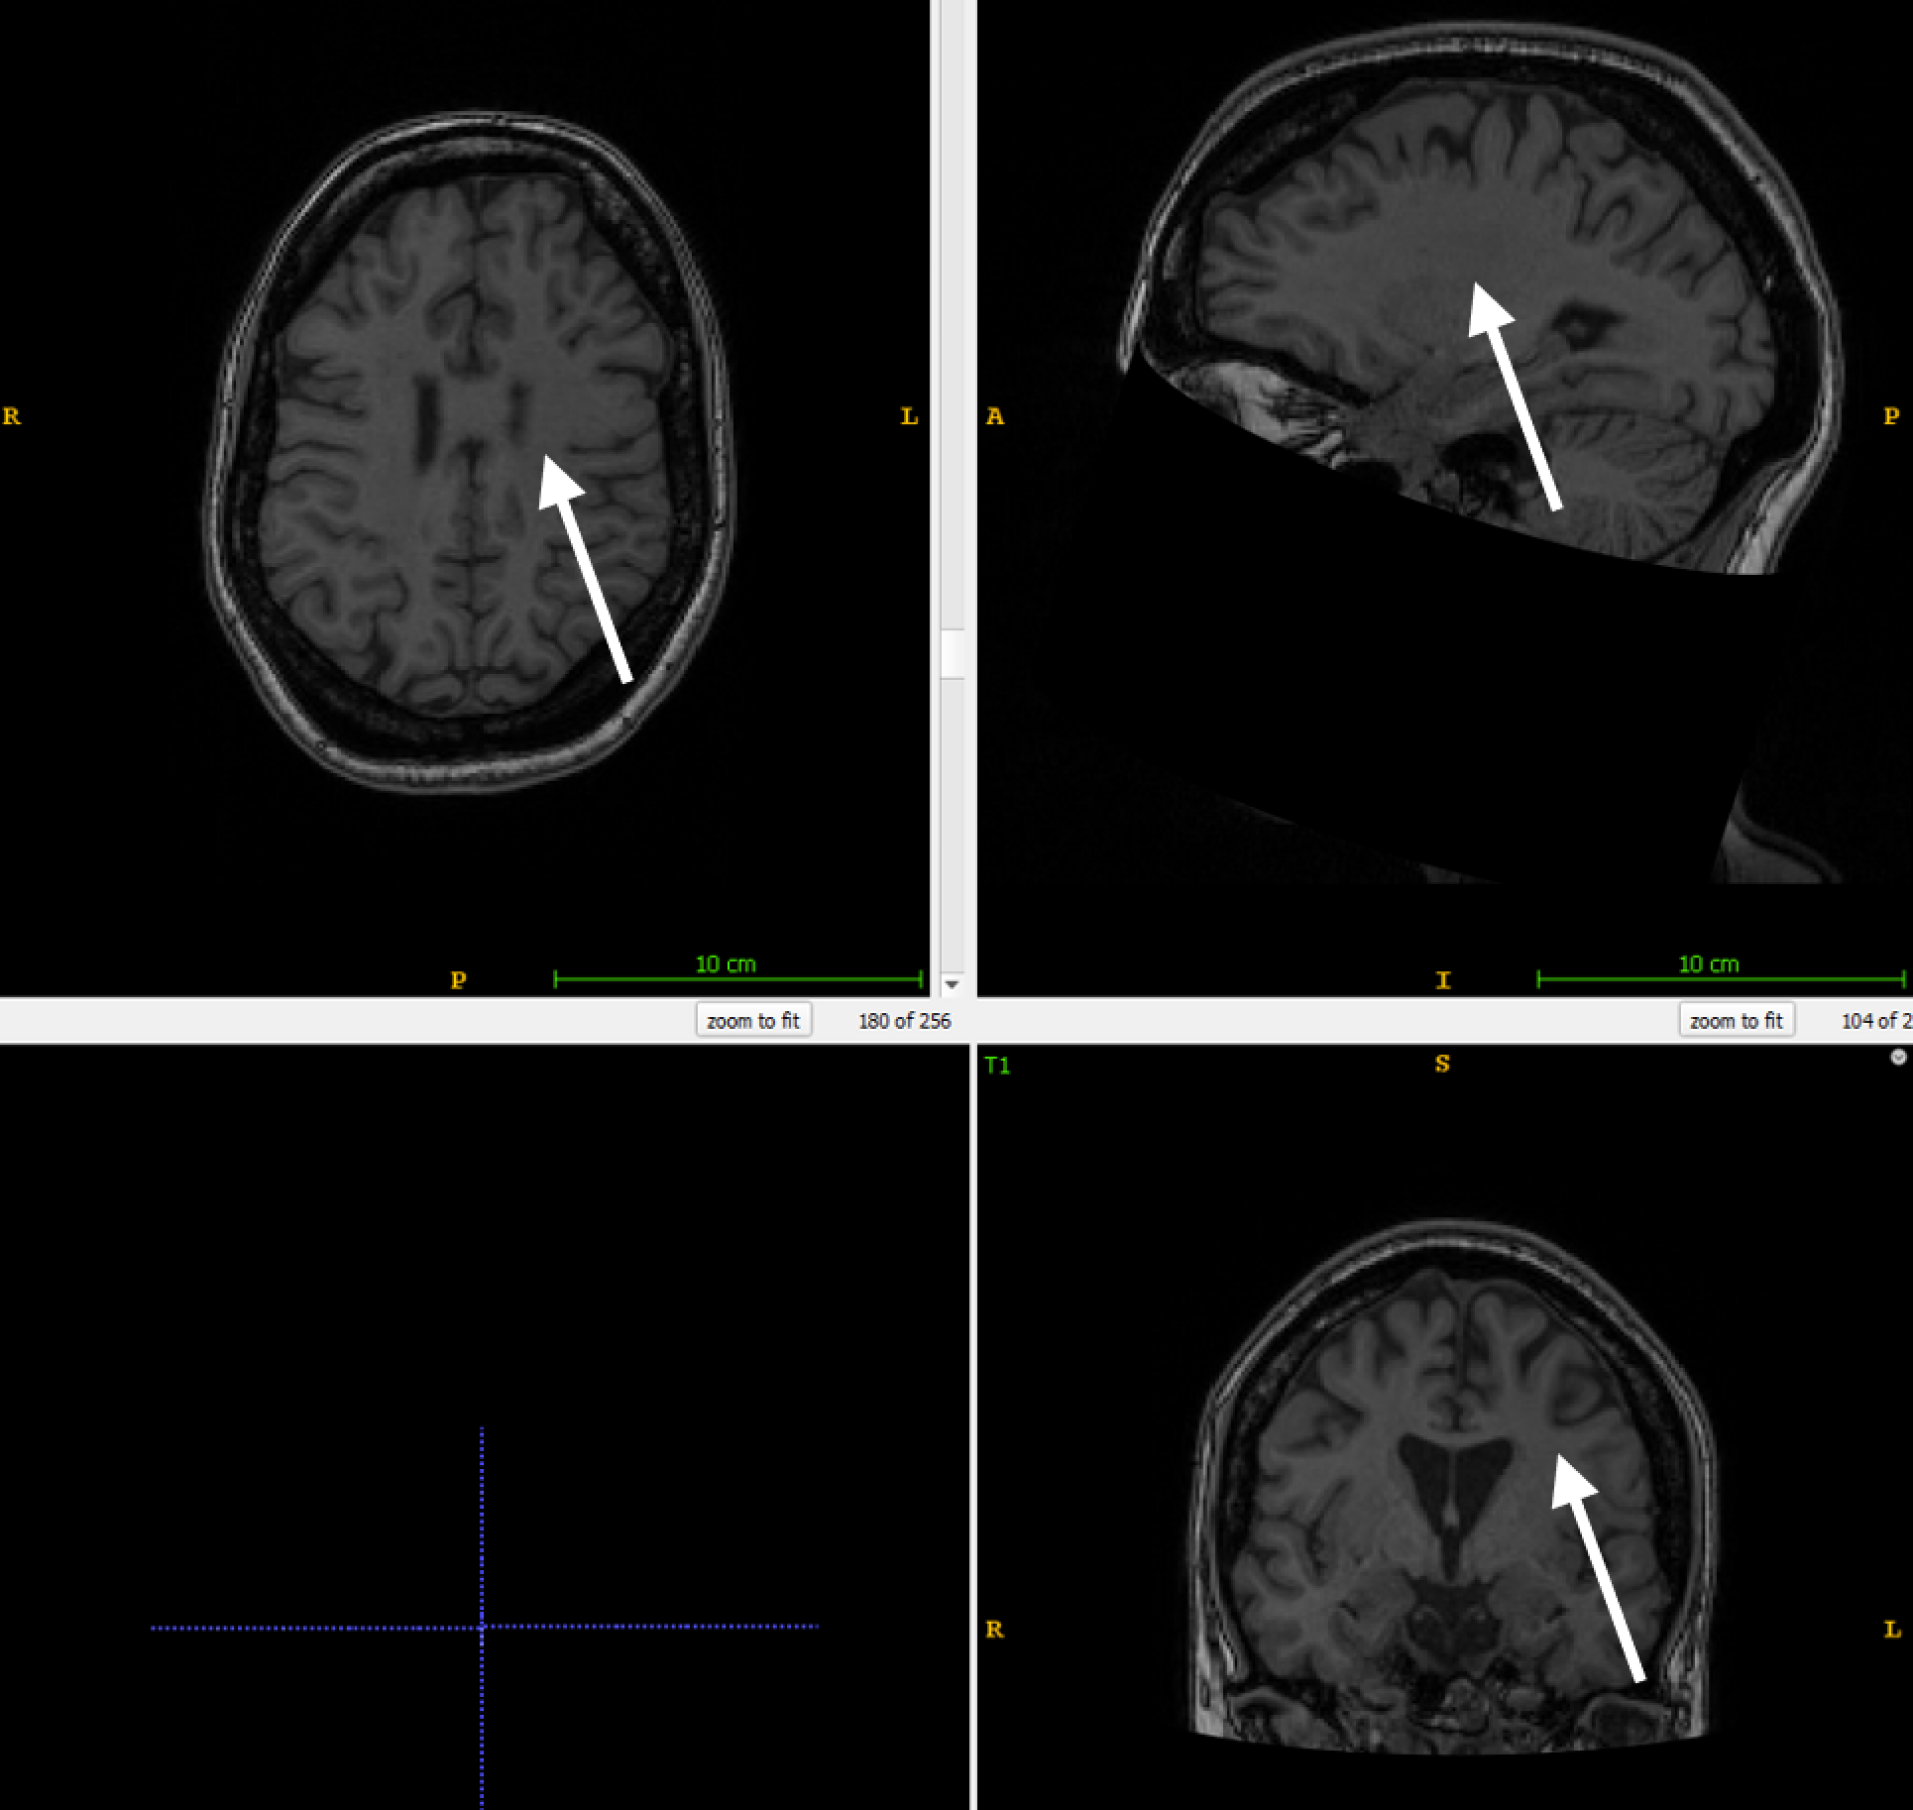

The impact of lesion filling on cortical thickness measurements was conducted using a test set composed of 65 patients diagnosed with RR-MS. This data originated from an internal longitudinal study conducted at the Insel hospital. All patients had been undergoing Natalizumab treatment for over two years and had at least four MRI scans performed over a period of approximately six months each, with corresponding clinical evaluations. MRI scans included a combination of 1.5T and 3T datasets with a slice thickness of 1mm or less in the T1w sequences. For each patient, the T1w and FLAIR images from their final visit, typically containing the highest lesion burden, were used for testing.

All T1w images undergo resampling to a standardized size of 256x256x256 voxels with a 1.0x1.0x1.0 mm voxel size and are reoriented to RAS orientation. FLAIR images are resampled to 160x256x256 voxels. The resampling process is carried out using nibabel.processing.conform [25]. Values below 0.01 are discarded as noise and the remaining data is scaled to the range [-1, 1]. A deep learning-based tissue segmentation is performed on the T1w images for each patient using the DL+DiReCT model [26]. To accelerate this process, the parallelization program GNU Parallel [27] is employed. For datasets with existing lesion masks, these are registered from FLAIR to T1w images using NiftyReg [28]. In the absence of lesion masks in the test set, a separate segmentation model DeepSCAN [29] is utilized to identify MS lesions. Only 2D slices containing WM, based on the DL+DiReCT segmentation, were incorporated for training.

Where N is the number of patients, the measurement before lesion filling, the measurement after lesion filling and the within-patient mean. This calculation is performed both for the global mean thickness (averaging the mean thickness of the left and right hemispheres) and across anatomical regions defined by the Desikan-Killiany (DK) atlas [42]. Since ANTs and ANTsPyNet do not deliver regional statistics, for those methods we average over the parcellation derived from DL+DiReCT. In a subanalysis, we excluded cases with MS lesions located near the cortical surface (juxtacortical lesions) which might lead to lesion-filling errors: to identify patients with juxtacortical lesions, the binary lesion masks are dilated by one pixel and multiplied with the tissue segmentations. Patients with lesions outside WM are excluded in the second analysis.